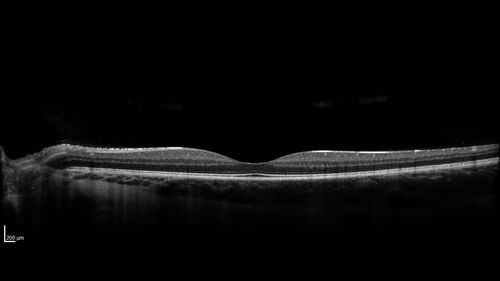

Traumatic Peripapillary Subretinal Hemorrhage

16 year old hit in eye with finger during basketball. Vision is 20/25 and there is a peripapillary hemorrhage.